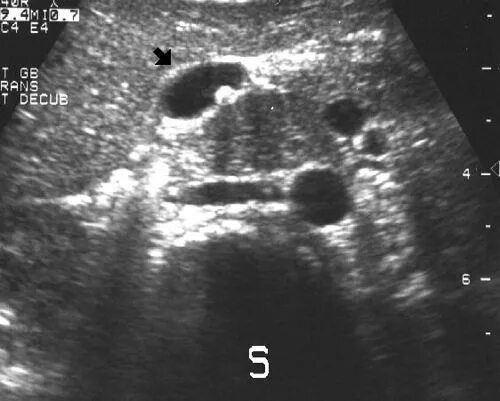

Как выглядит узи живота